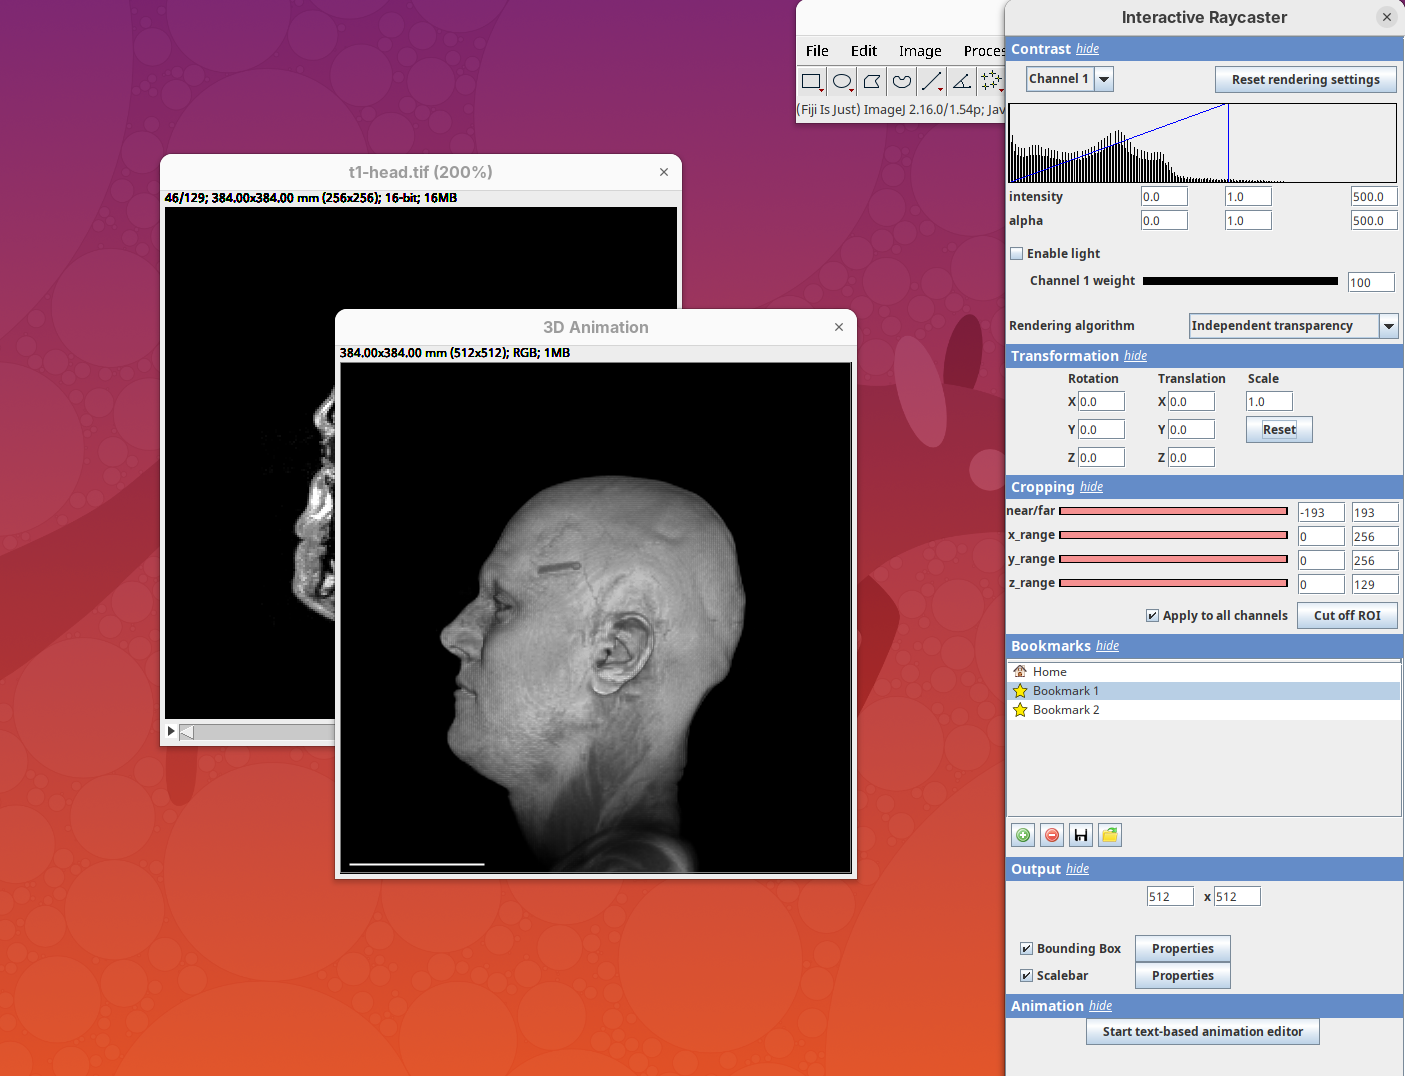

Output

This last panel defines the dimensions of the output animation. By default it uses the original stack dimensions.

You can also define if the bounding box or the scale bar will be visible (enabled by default).

Animation 3D

Now that we learned the basics of setting up the rendering and view parameters, we can start generating animations of the data.

- Click on the

Animationsection and on theStart text-based animation editorbutton.

This will open a special editor window for writing the animation script.